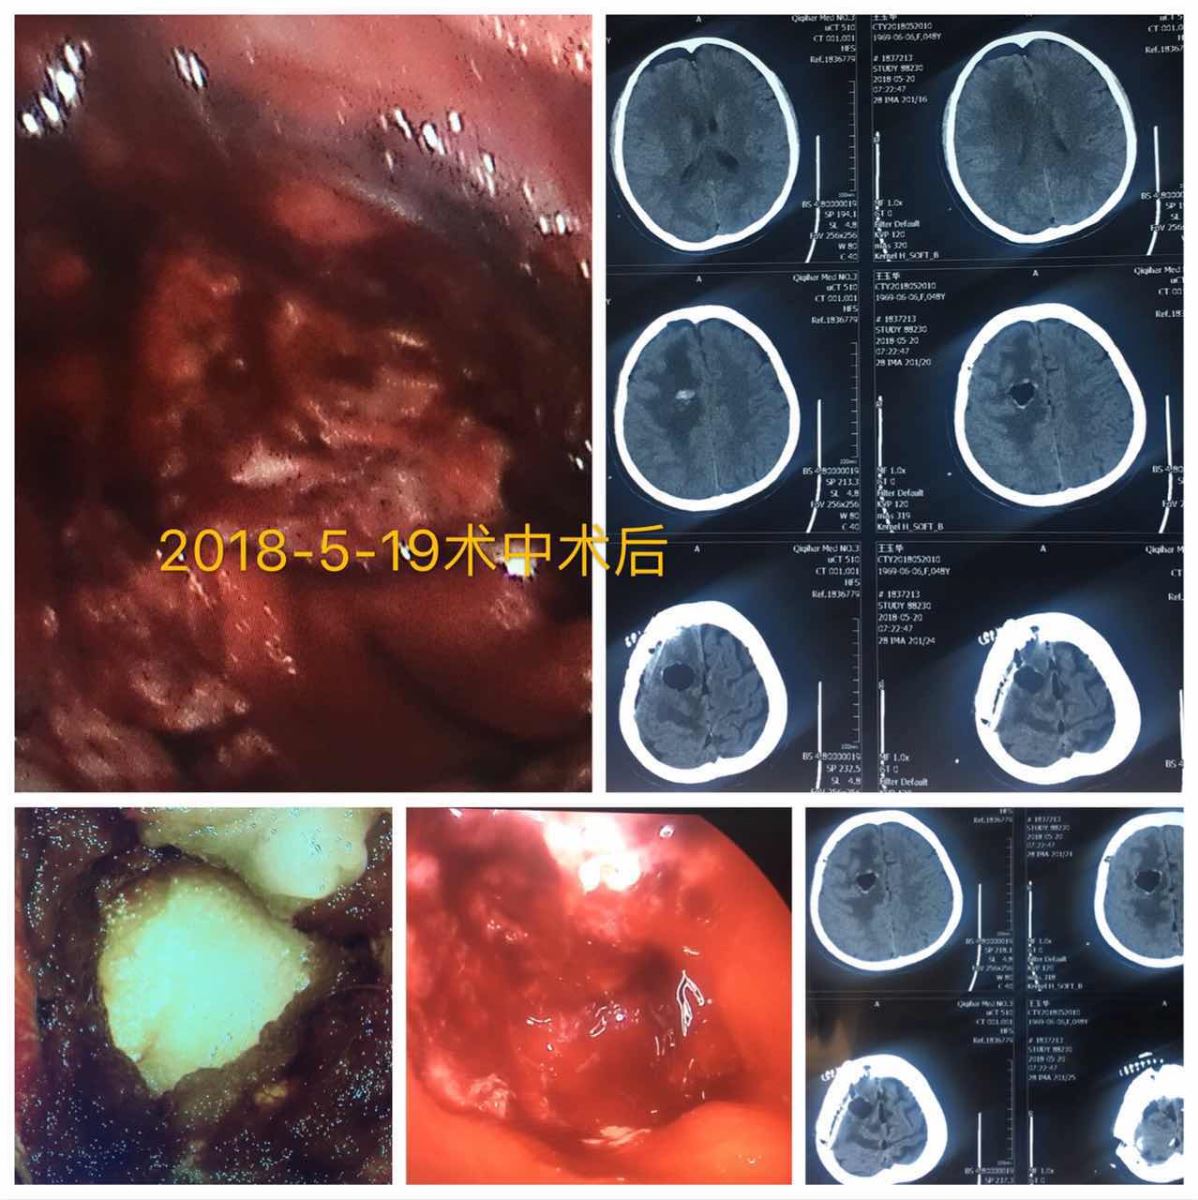

患者王女士,因“左侧肢体麻木1周”入院,诊断为颅内占位,在神经内镜辅助下切除病变部位,患者术后肢体麻木感消失,四肢活动良好。

影像图片

第一例脑室镜颅内感染脑室灌洗术+透明隔造瘘术影像图片